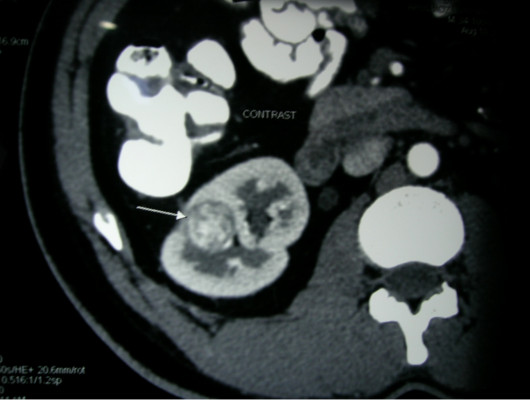

The purpose of testing is to diagnose and stage the Tumour :

Stage I – a tumour less than 7cm in the kidney.

Stage II – a tumour larger than 7cm in the kidney.

Stage III – a tumour in the kidney and nearby lymph nodes, main blood

vessels and tissues.

Stage IV – cancer may spread to other organs through blood vessels

and lymph nodes.